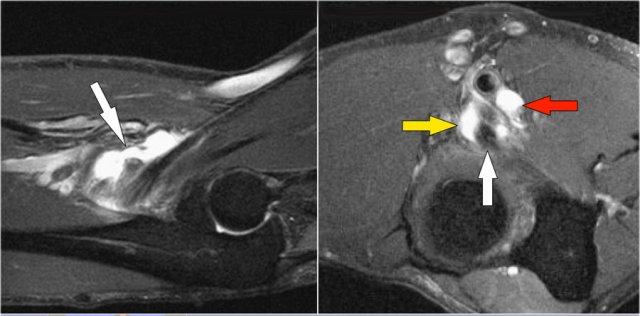

Đây là hình ảnh MRI.

Coronal view:

- Dây chằng bên ngoài bị bóc tách hoàn toàn (mũi tên vàng).

- radial head is subluxed.

- phù tủy xương của mỏm vẹt do gãy xương (mũi tên đỏ).

Sagittal view:

- Chỏm xương quay bị bán trật nhẹ ra phía sau (mũi tên vàng).

- Large effusion and capsular disruption posteriorly.

- Đụng dập mặt sau của chỏm con do va chạm với mỏm vẹt (mũi tên đỏ).

All these signs are the result of a posterior dislocation.